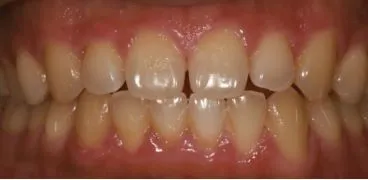

건강한 잇몸이란?

먼저, 잇몸에 대해 알아보겠다. 잇몸은 치아를 둘러싸고 지지하는 조직으로, 치은·치조골·치주인대·백악질로 구성된다. 건강한 잇몸은 선홍색을 띠며 치아에 단단히 부착되어 있고, 염증이 없으며 칫솔질시 출혈이 나타나지 않는 것이 특징이다.